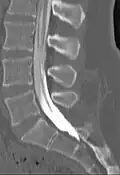

Myelogram showing arachnoiditis in the lumbar spine.

Myelography is a type of radiographic examination that uses a contrast medium (e.g. iodised oil[1]) to detect pathology of the spinal cord, including the location of a spinal cord injury, cysts, and tumors. Historically the procedure involved the injection of a radiocontrast agent into the cervical or lumbar spine, followed by several X-ray projections. Today, myelography has largely been replaced by the use of MRI scans, although the technique is still sometimes used under certain circumstances – though now usually in conjunction with CT rather than X-ray projections.[2]